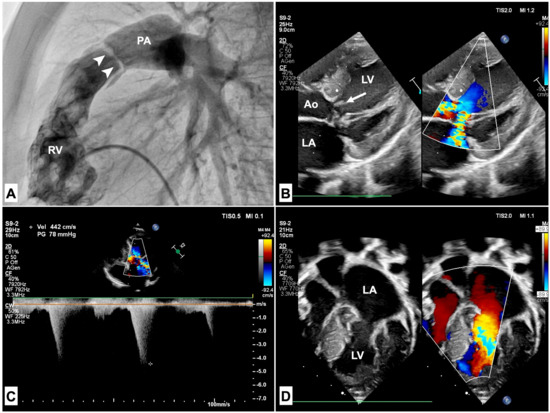

3.1. Pulmonary Stenosis

- Holzmann, J.; Tibby, S.M.; Rosenthal, E.; Qureshi, S.; Morgan, G.; Krasemann, T. Results of balloon pulmonary valvoplasty in children with Noonan’s syndrome. Cardiol. Young 2018, 28, 647–652. [Google Scholar] [CrossRef] [PubMed]

- Abumehdi, M.; Mehta, C.; Afifi, A.; Yong, S.F.; Chaudhari, M.; Bhole, V.; Dhillon, R.; Stumper, O. Supravalvular pulmonary stenosis: A risk factor for reintervention in Noonan syndrome with pulmonary valve stenosis. Catheter. Cardiovasc. Interv. 2022, 99, 1538–1544. [Google Scholar] [CrossRef] [PubMed]